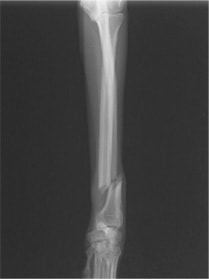

橈尺骨骨折 : 症例1 | 症例2 | 症例3 | 症例4 | 症例5 | 症例6 | 症例7

: 症例8 | 症例9 | 症例10 | 症例11 | 症例12 | 症例13 | 症例14

: 症例15 | 症例16 | 症例17 | 症例18 | 症例19 | 症例20 | 症例21

トイプードル 右遠位橈尺骨短斜骨折のALPSによる内固定